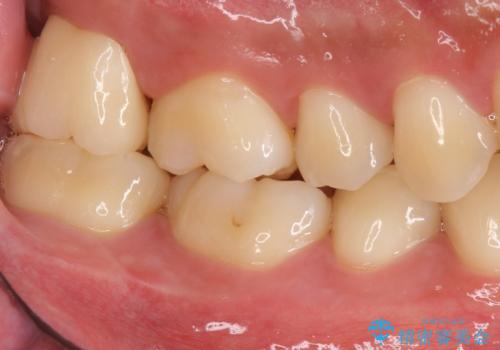

- 銀歯を白くしたいとのことで来院されました。

歯を覆っている銀の詰め物の面積が広く、セラミックで同じ形態にすると強度に不安が残るため被せ物での修復処置を行っていきます。

ブラッシングが上手な患者様であったため歯茎の締りもよく、大変適合の良い被せ物を装着することができました。